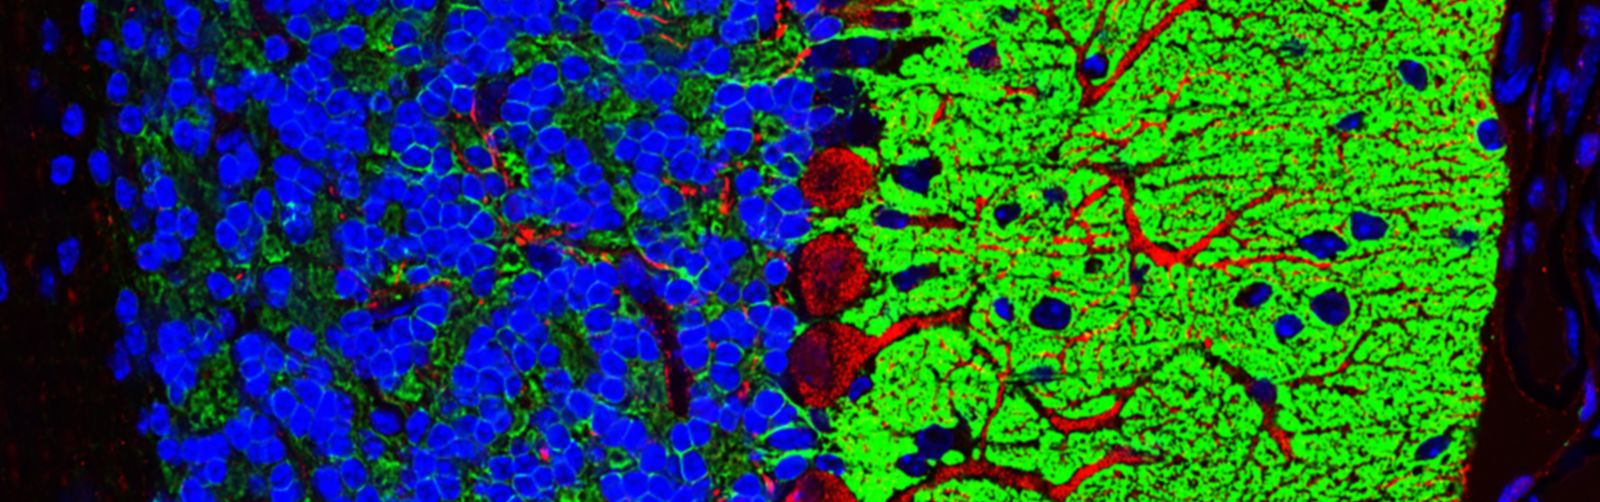

The UMass Chan Medical School light microscopy core facility, the Sanderson Center for Optical Experimentation (SCOPE), offers the tools and expertise required to perform a wide variety of quantitative microscopy techniques including super resolution imaging, multi-photon intravital and live tissue imaging, confocal microscopy and high-speed time-lapse imaging. The SCOPE offers a combination of commercial and custom-built microscopes, allowing users to address an extensive array of biological questions.